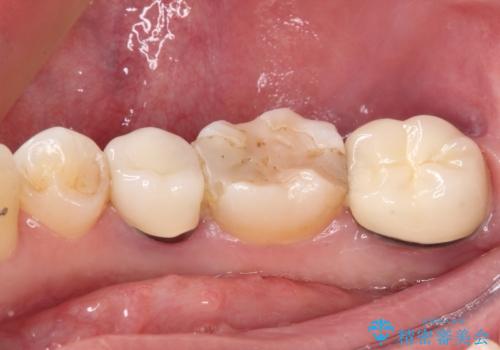

- ヨーロッパ駐在期間中に治療を受けた歯がしみるとのことで来院された患者様です。

ドイツやベルギーなどで治療を受けた奥歯2本が食事の度にしみているとのことで、レントゲン検査や視診を行ったところ、補綴物や修復物の適合が悪く、それが原因であると考えられました。

いずれの歯も症状に異常なく、オールセラミッククラウンにて補綴治療を行うこととしました。